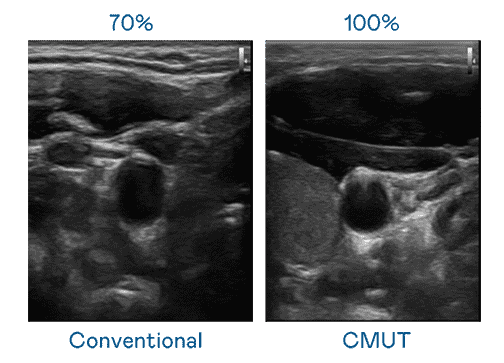

CMUT 技术是一种用电容式微机电元件来产生超音波讯号的技术。。。。与传统 PZT 压电式技术相比,,,,CMUT 频宽增加 30%,,更宽频的超音波讯号让影像解析度大幅提升,,,,是实现高影像品质医疗超音波扫描、、、、促进精准医疗发展的关键技术。。

大频宽带来超清晰影像

超音波影像的解析度高低,,,首先取决于探头能发出的讯号频宽。。。。人生就是博 CMUT 可提供高清晰的超音波讯号,,,提供高频宽、、、高灵敏度、、、影像纹理细节更高的超音波影像,,,协助医护人员缩短影像判读时间及利用精准的医疗影像进行诊断。。